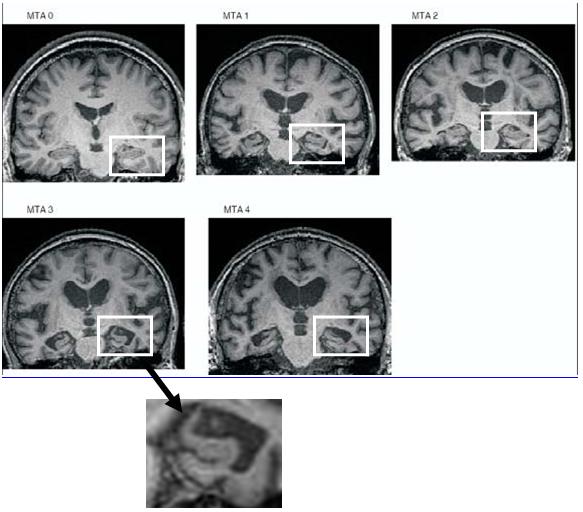

Při výzkumné činnosti jsme adaptovali zahraniční systém hodnocení velikosti hipokampu pomocí tzv. skóre MTA (mediotemporální atrofie). Skóre je podobné známkování ve škole od 0 (nejlepší, normální objem hipokampu) do 4 (nejhorší, scvrklý hipokampus). Zkušenosti s tímto typem hodnocení jsme zveřejnili v odborném článku a nyní ho používáme již rutinně. Naše práce na měření objemu hipokampu získala cenu za nejlepší plakátové sdělení na kongresu v Nice, 2008.

Níže uvádíme příklady různě objemných hipokampů na obrázcích z MR mozku.

Ukázkové snímky MR mozku z naší činnosti se všemi 5 stupni mediotemporální atrofie (MTA) od žádné (0) až po masivní (4).